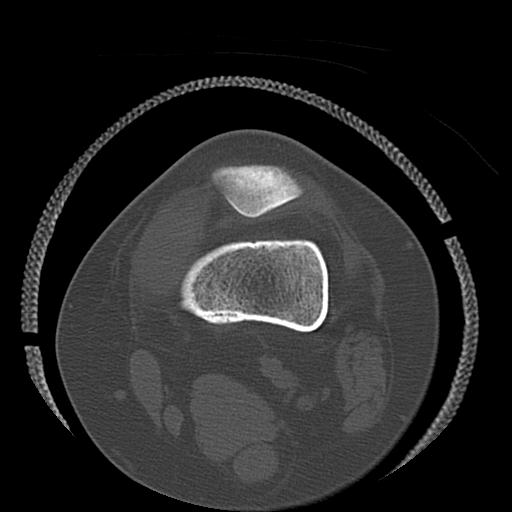

49554 3/13 膝 4R 3/16 4R 1/18 2R 78歳男性 膝蓋骨骨折